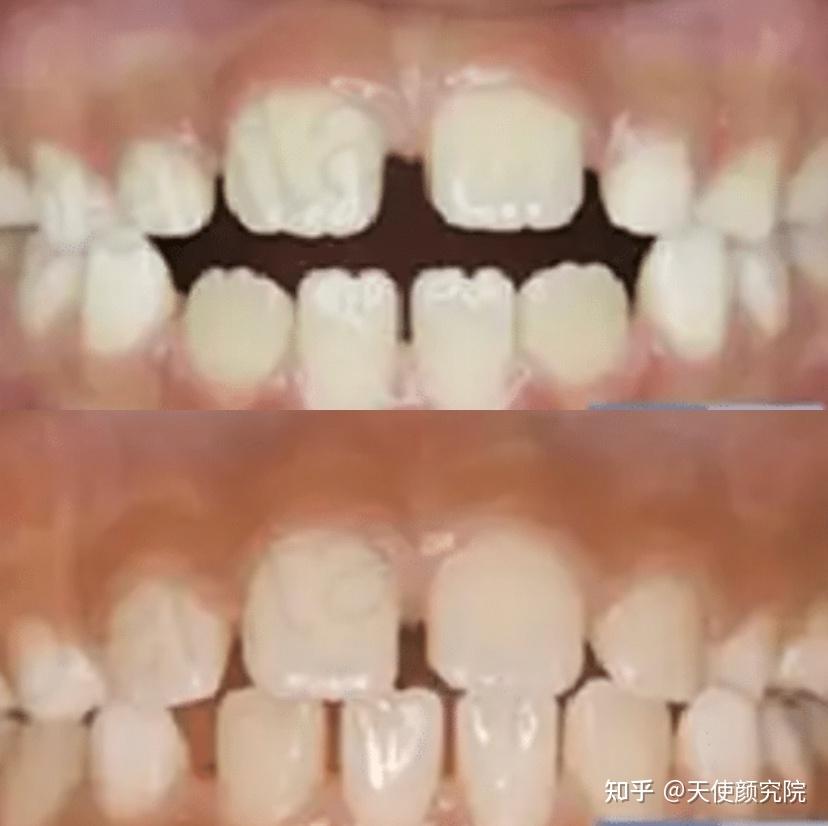

最近还刷到了JK姐妹的儿时照,其实仔细看看秀妍很小就有颌面问题的迹象了,秀妍牙齿导致的颌面问题早就给后期”调整“埋下了种子。

不过还好,西卡父母最后带她去做了矫正,现在已经是牙齿矫正的受益人啦。(因为练习生+出道较早,所以留下一些before照片)